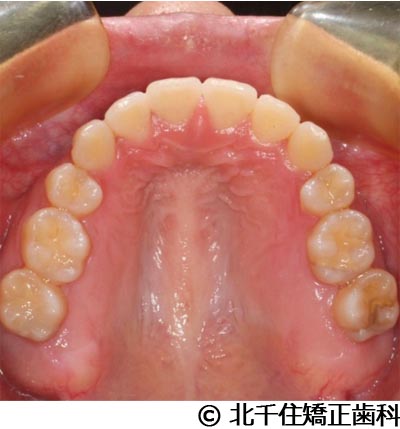

- 治療前

- 治療後

- 治療名

- 叢生

- 費用

- 1,125,000円(税込)

- 期間

- 2年1ヵ月

- 治療回数

- 26回

- 通院頻度

- 1ヵ月ごと

- 年齢・性別

- 19歳3ヵ月・女性(初診時)

治療内容

患者様の症状

主訴:デコボコ、口元の突出

治療方法

上下顎第一小臼歯4本を抜歯してワイヤー矯正(セラミックブラケット)。

治療結果

叢生に対し抜歯を併用した矯正治療により、歯列および咬合関係の調整を行った症例である。治療後は保定装置を使用し、歯列および咬合の安定維持を目的として定期的な経過観察を行っている。

※治療結果は個人差があります。

治療を行う上での注意点(リスク・副作用)

歯磨き不良に伴うカリエスや歯周病、歯根吸収など。